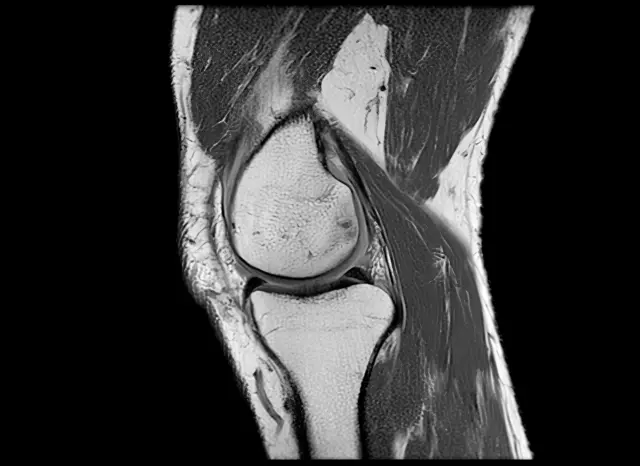

«La rodilla es una de las articulaciones más complejas de todo el cuerpo», le dice a la BBC Anikar Chhabra, un cirujano ortopédico especializado en medicina deportiva de la Clínica Mayo en Phoenix, EE.UU.

Nuestras rodillas dependen especialmente de cuatro grupos de músculos que las rodean: los isquiotibiales, los de los glúteos, los cuádriceps y los músculos de la pantorrilla.

Esos grupos de músculos le permiten estabilidad y le dan la capacidad de absorción para poder funcionar.

«Cuando esos músculos no están interactuando y trabajando juntos, la articulación recibe más presión. Ahí es cuando comenzamos a sentir el dolor», señala Chhabra.